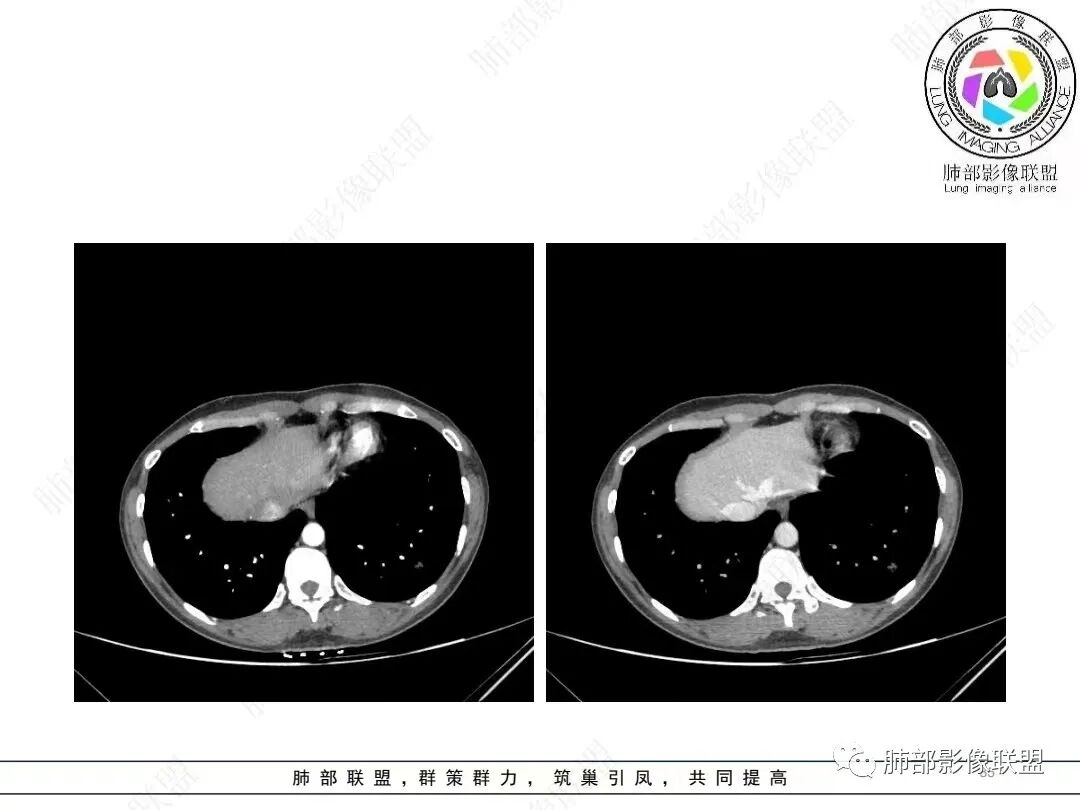

肺动脉供血

@张明辉临沂市人民医院 今天病例粗大肺动脉供血+空洞结节,和我上传病例比较像。

2、影像特点:左肺下叶类圆形结节影,周围可见多发细小毛刺,浅分叶,张力不高,未见胸膜牵拉。病灶内隐约见空泡影(未提供CT值),近端部分血管呈杵状增粗,可疑脐凹征。增强后实性部分有轻度强化。外围病灶,与支气管关系不明确。